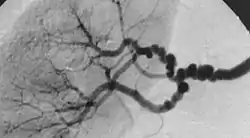

![]() شكل "خيط السبحة" في خلل التنسج الليفي العضلي متعدد البؤر، وتحدث بسبب مناطق التضيق النسبي بالتناوب مع تمدد الأوعية الدموية الصغيرة. شكل "خيط السبحة" في خلل التنسج الليفي العضلي متعدد البؤر، وتحدث بسبب مناطق التضيق النسبي بالتناوب مع تمدد الأوعية الدموية الصغيرة. | |

النوع الثاني هو التنسج الليفي المتعدد البؤر الذي ينطوي على تكثيف الوسط وتشكيل الكولاجين، وعادة ما يتم الإبلاغ عن وجود "خيط السبحة" في مراجعة الصورة الوعائية،[4] "السبحة" غالبًا ما تكون أكبر من التجويف الشرياني الطبيعي، وفي مجموعة فرعية من مرضى يحدث تمدد الأوعية الدموية وقد تتطلب العلاج،[4] ويشغل النوع الفرعي متعدد البؤر من FMD ما يقرب من 80٪ إلى 90٪ من جميع الحالات FMD [4] (المعروف سابقًا باسم الإنسي).